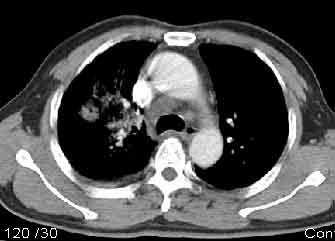

该病例我的诊断意见:右肺上叶周围型肺癌伴纵隔和右肺门淋巴结增大和右肺上叶阻塞性肺炎{病灶周围致密影以近肺门侧明显!}。右侧少量胸腔积液。

一. 1)症状有无发热及慢性过程.2)化验室检查?3)有无tb接触史?二.右肺上叶见片团状影,边界欠清,外侧方见一结节状软组织影,密度欠均匀,内可见低密度坏死区.周围强化明显,肺内见纤维索条影,局部胸膜增厚,但无明确胸膜凹陷.上叶支气管壁增厚,肺门及纵隔淋巴结增大.右侧胸腔少量积液.诊断意见:1右肺上叶慢性感染性疾病(肺tb?)伴肺门,纵隔淋巴结大.右胸少量积液.右肺上叶结节影多为tb球?2右肺上叶周围型肺ca伴肺门,纵隔淋巴结转移待排.右肺上叶炎变(肺门及纵隔淋巴结压迫).右胸少量积液.等待随返结果.